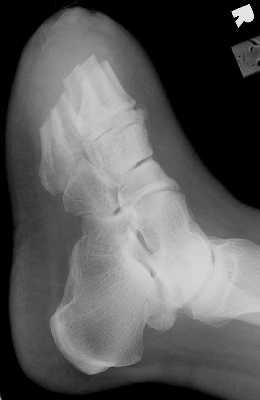

Another transmetatarsal amputation.